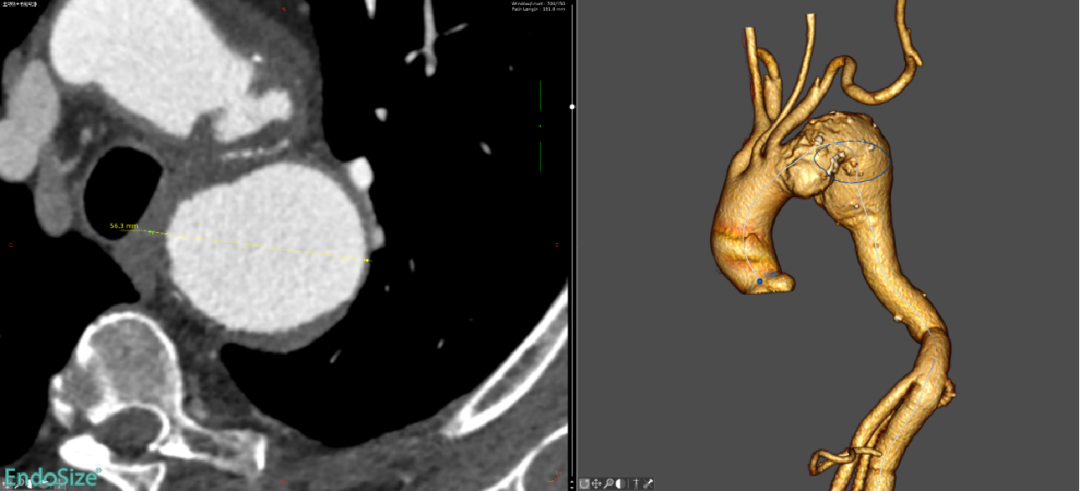

纳入2022.12月-2023.8月长海医院11例男性患者(平均年龄63.2岁),其中动脉瘤64%(7例)、夹层36%(4例)。

术后12个月CT血管造影(CTA)随访显示,支架移植物位置稳定,无明显移位或变形,分支血管通畅。

First-In-HuMan study--CTA

CTA preoperation

CTA 12 monthes FU